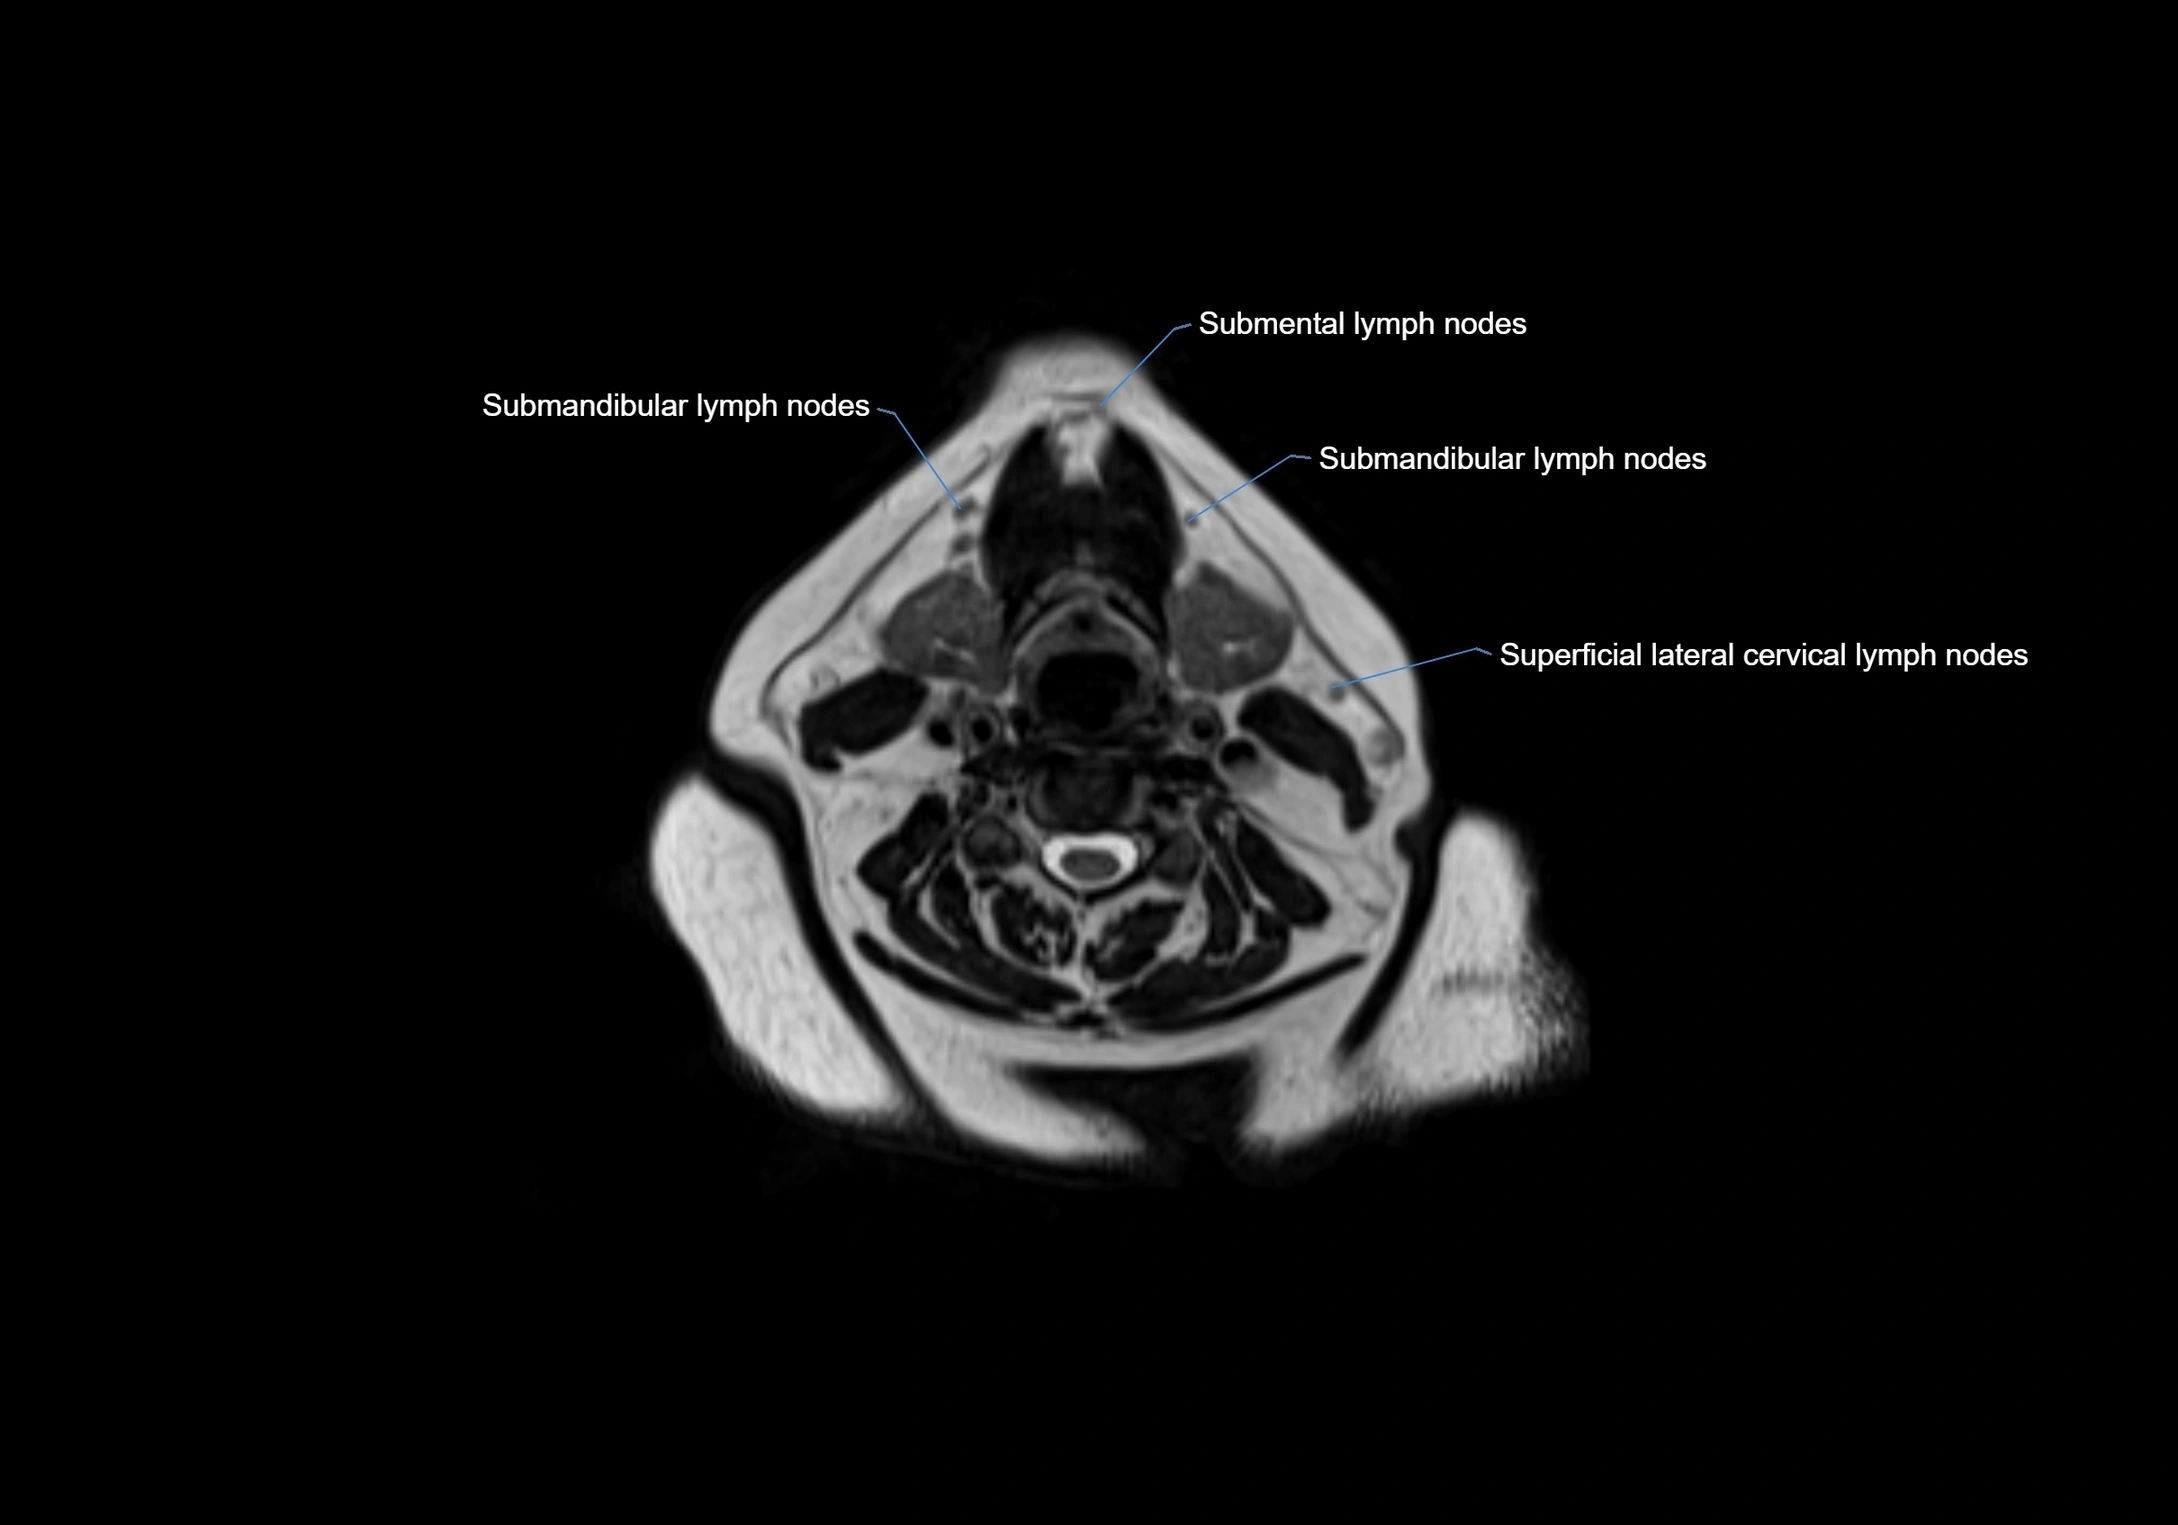

Accessory lymph nodes

Accessory lymph nodes are small, secondary lymph nodes located along the main facial and cervical lymphatic chains, often adjacent to primary lymph nodes, such as preauricular, submandibular, or occipital nodes. They are typically less than 5 mm in diameter, embedded within subcutaneous fat or connective tissue, and may be variable in number and location. These nodes provide additional filtration and immune surveillance for lymph collected from the face, scalp, and neck regions. Accessory lymph nodes are usually non-palpable in healthy individuals but may enlarge in response to infection, inflammation, or metastasis, making them clinically significant.

Location

• Found along primary lymph node chains, including preauricular, submandibular, parotid, and occipital regions

• Embedded in subcutaneous fat or superficial fascia, often lateral or posterior to primary nodes

• Variable in number; may occur unilaterally or bilaterally, depending on individual anatomy

MRI images

image